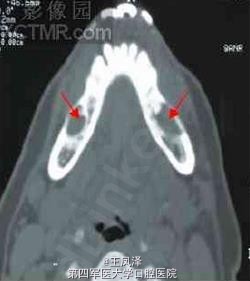

上、下颌骨囊肿CT诊断学

患者女性,49 岁。主诉:右侧后下牙痛近1 年。CT 下颌骨轴扫示:双下颌骨体部齿源性囊肿。术后病理证实。